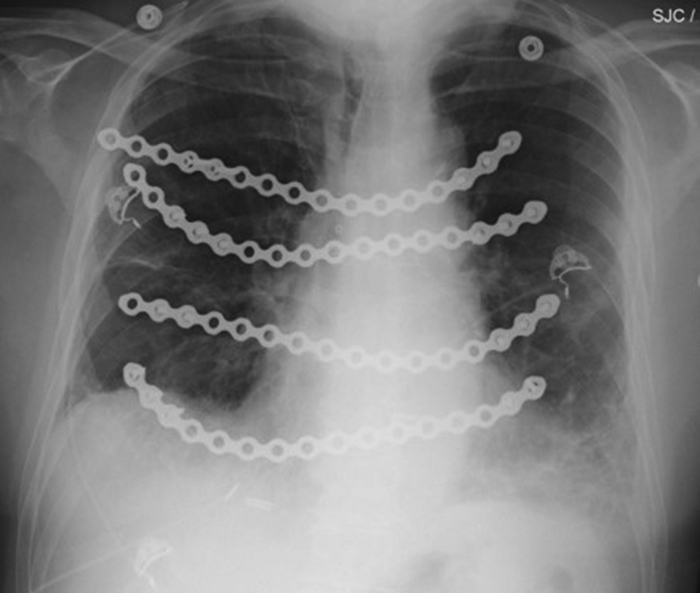

Surgical fixation apparatus - plates, screws, cages, rods, nails, prosthesis - most commonly cause signal loss and photopenia on nuclear medicine studies from their absorption or scatter of radiotracer photons originating deeper in the body. Sometimes, they may stimulate bony healing or bony reaction with an increase in radiotracer signal (figure 35).

| PA Chest radiograph (A) demonstrates a sternal cage. Whole body Tc99m MDP images (B) demonstrate focal radiotracer activity in ribs bilaterally on the anterior view representing the sites of sternal cage fixation with bony reaction. |